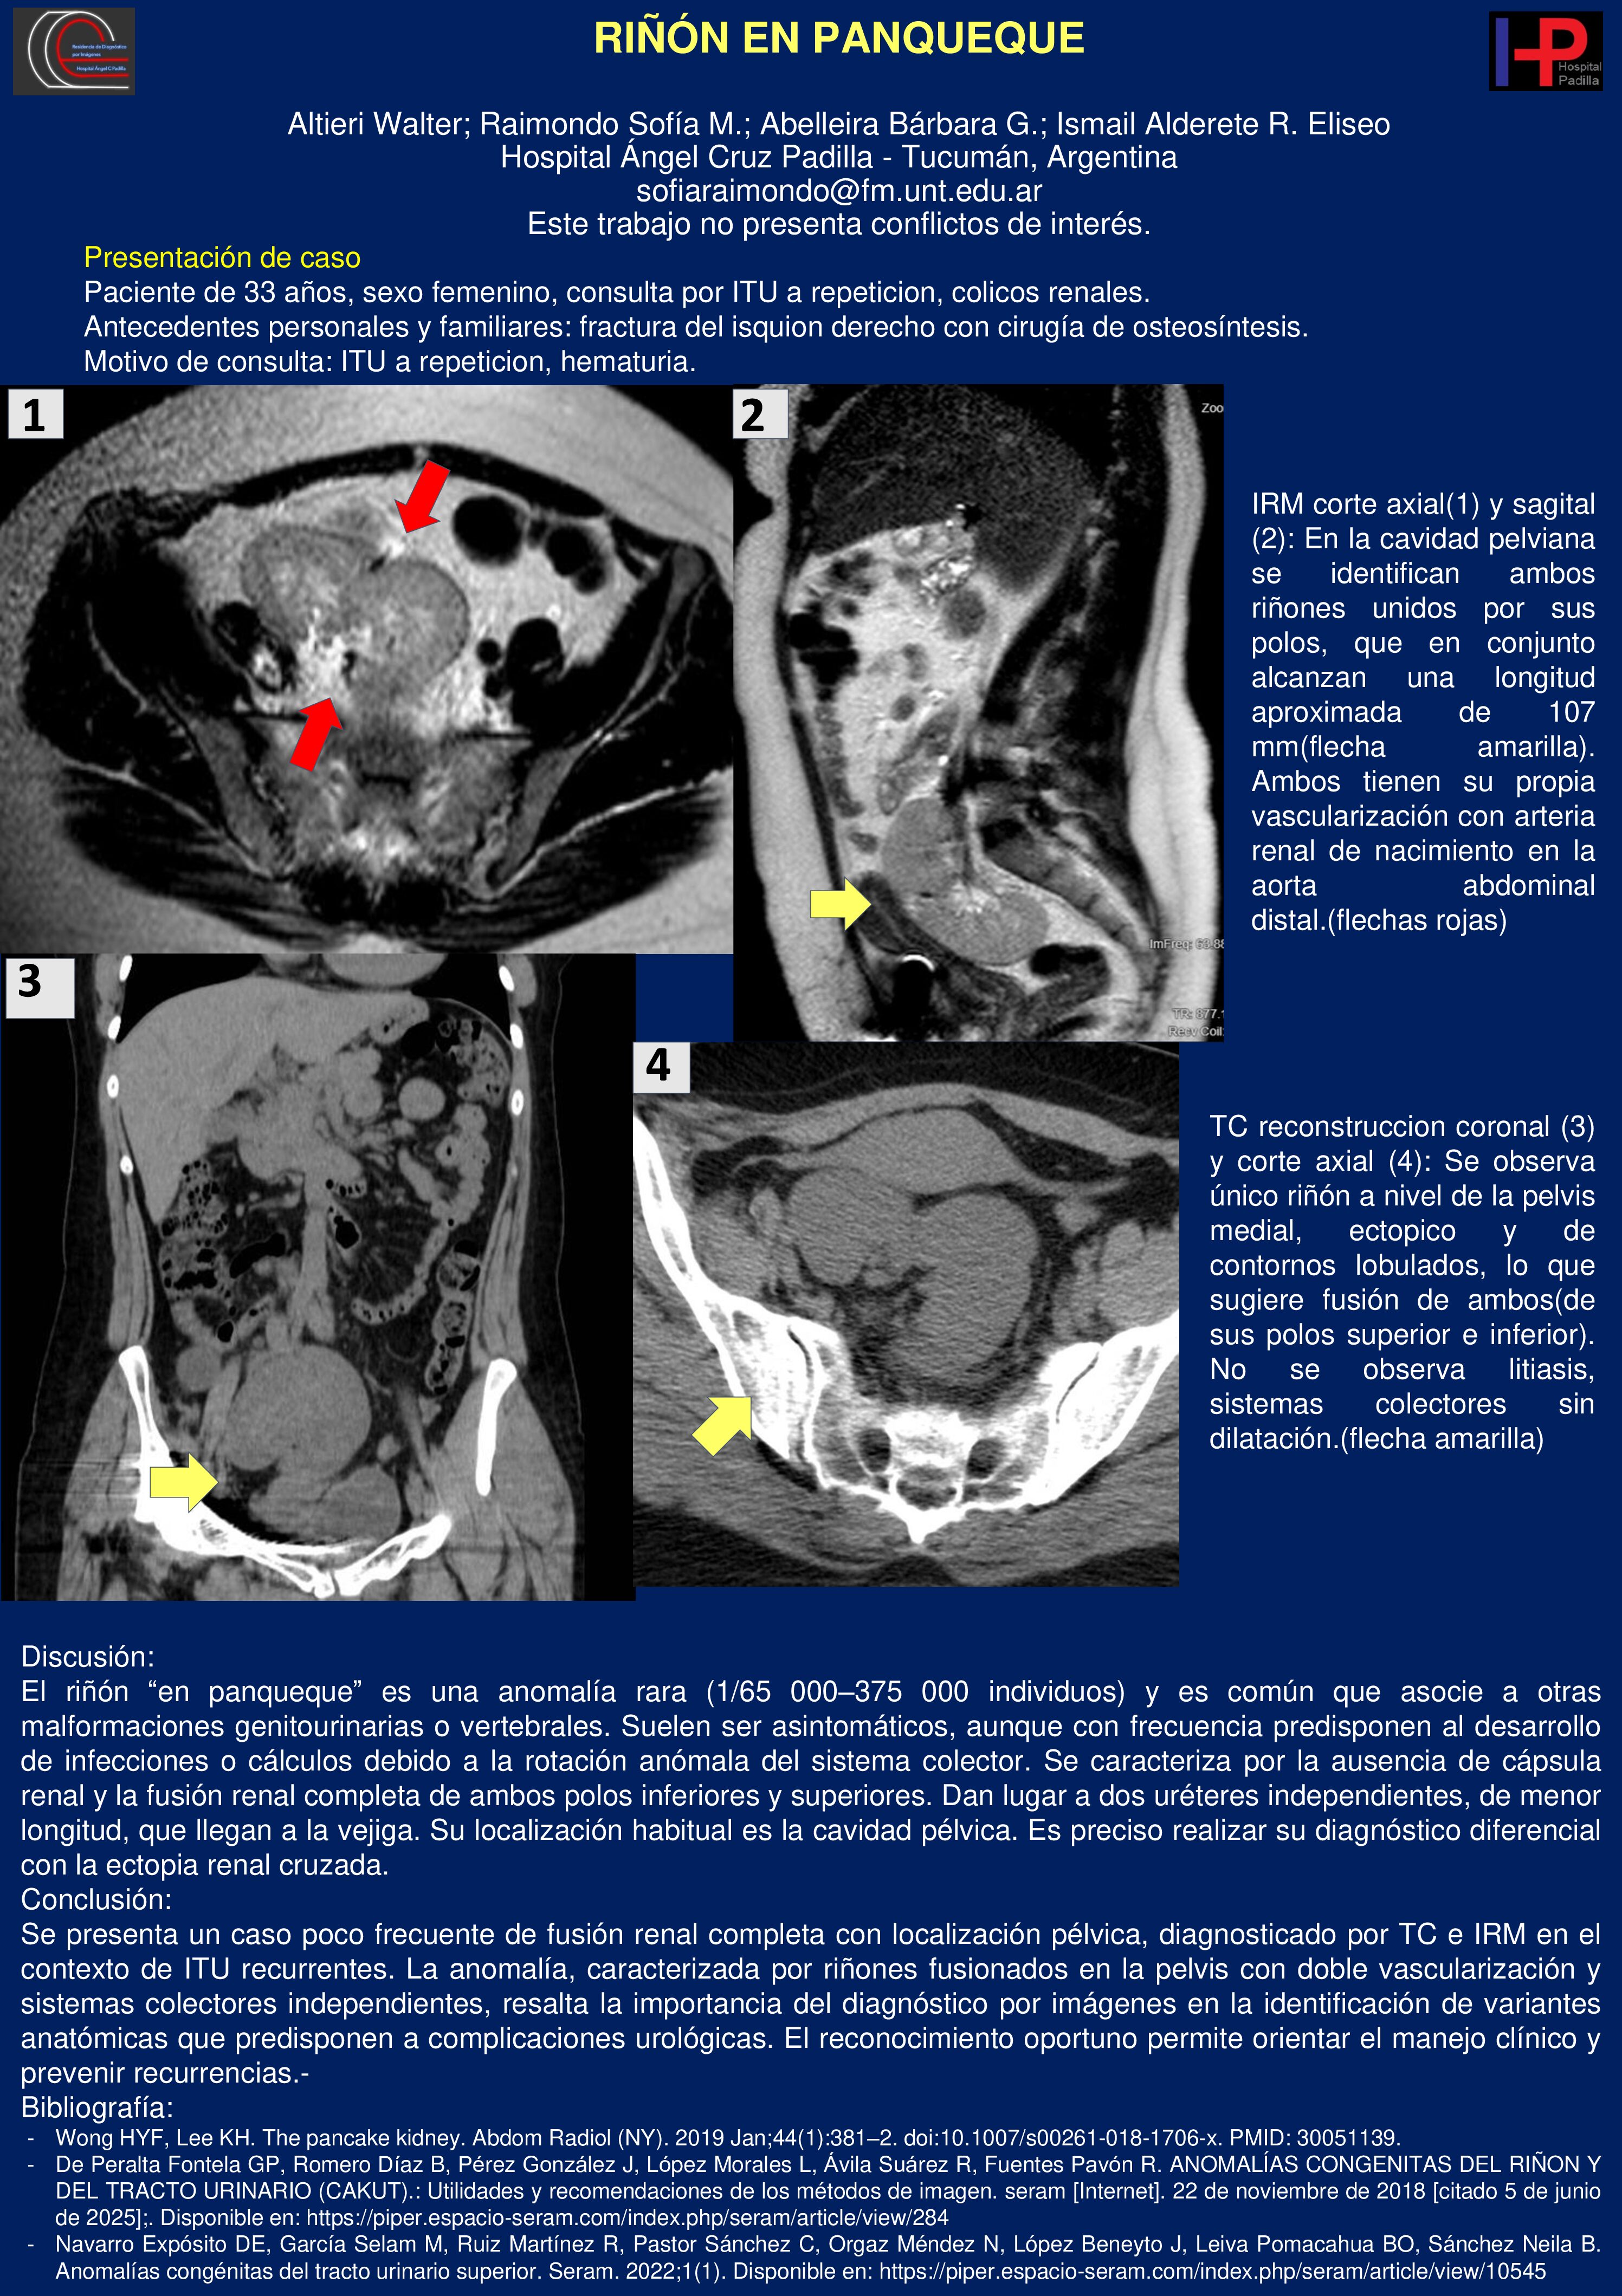

RIÑÓN EN PANQUEQUE